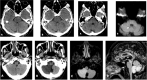

Figures